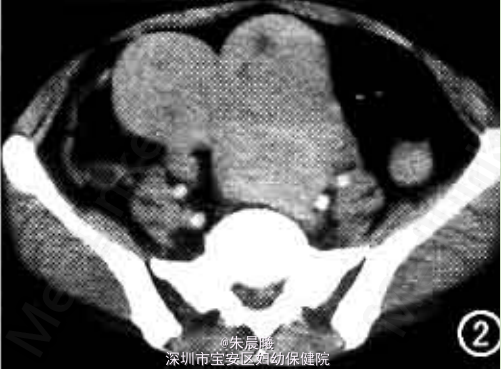

查体:腹膨隆,可触及盆腔包块达脐上两横指,质硬、无压痛,子宫及附件扪及不清。 实验室检查无异常。 静脉肾盂造影见中下腹13 cm×24 cm和11 cm×13 cm大小包块,呈哑铃状,边缘界限清楚。左侧包块内布满爆米花样钙化,输尿管受压右移,未见阻塞;右侧积尿系轻度扩张,膀胱左侧受压变形,CT平扫加增强如图1、2。

诊断:盆腔包块待查:子宫肌瘤? 治疗:此病例予开腹手术,手术见子宫巨大肿瘤及右侧附件阔韧带区肿瘤,肿物与子宫底有索条状蒂相连,大小分别为30 cm×20 cm×20 cm和12 cm×12 cm×12 cm,重3妇,实性,有包膜。病理诊断:①子宫多发性肌瘤,可见玻璃样变;②慢性宫颈炎;③(右)卵巢、输卵管组织。

随访:子宫多发肌瘤易反复,约1/3患者需再次手术,术后定期复查B超。 讨论:子宫肌瘤90%以上生长于子宫体部,仅有4%~8%发生于子宫颈,且多在后唇。在体部者多长于子宫底,后壁次之,位于前壁者比后壁少一半,而以两侧者最少。肌瘤的类型以壁问肌瘤最多,浆膜下肌瘤次之,粘膜下肌瘤比较少见。本例盆腔巨大包块为多发浆膜下肌瘤,并向右侧附件阔韧带区伸展,带蒂,形成阔韧带肌瘤,实性部分内可见不规则钙化。阔韧带平滑肌瘤少见,CT表现为密度均匀或不均匀的软组织肿块,CT值与子宫肌瘤相似,增强扫描呈明显强化,坏死、液化部分不强化。本病例由于肿瘤大、肿瘤内部密度不均匀出现爆米花样钙化而误为卵巢病变,遇到类似病例表现,要想到浆膜下子宫肌瘤可向子宫旁伸展或向周围寄生。